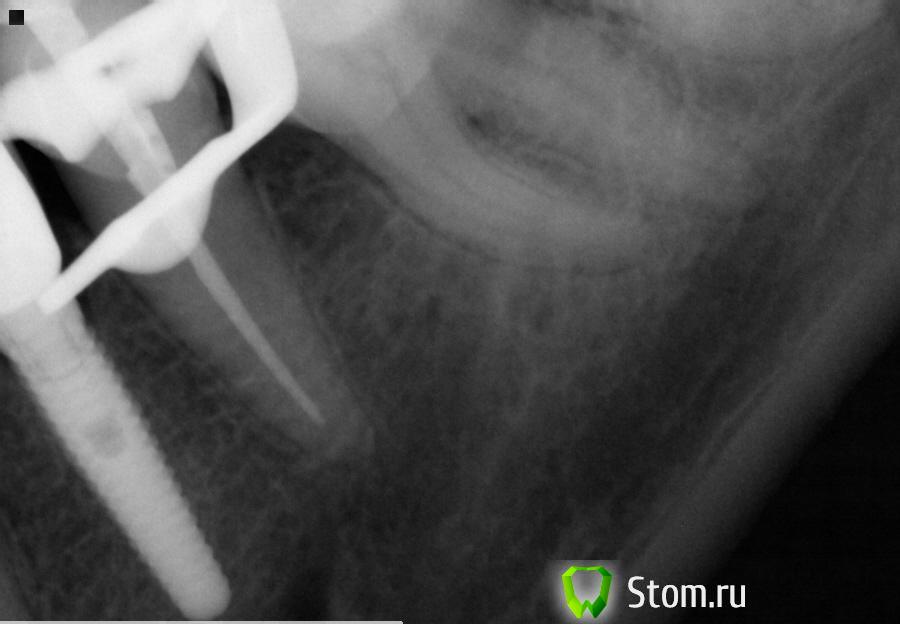

x3m Опубликовано 2 декабря, 2011 Поделиться Опубликовано 2 декабря, 2011 снимок повесьте.настораживают боли, температурная чувствительность и не до конца запломбированный канал. Ссылка на комментарий

Celice Опубликовано 15 декабря, 2011 Автор Поделиться Опубликовано 15 декабря, 2011 Вот наконец принесла снимок. Скажите пожалуйста:- может этот зуб реагировать на холодное/горячее?- стоит ли его перепломбировывать? канал имхо не до конца пройден. Кстати, врач на вопрос: коронку менять будем? ответил: а зачем? т.е он считает что можно и так оставить. Может предложить ему за свой счет переделать? Ссылка на комментарий

DokDent Опубликовано 19 декабря, 2011 Поделиться Опубликовано 19 декабря, 2011 Никто не отвечает.. что, всё плохо, да? Да лучше бы перелечить. Ссылка на комментарий

juli63 Опубликовано 23 декабря, 2011 Поделиться Опубликовано 23 декабря, 2011 сколько каналов в зубе было? а что с соседним ? Ссылка на комментарий

Celice Опубликовано 23 декабря, 2011 Автор Поделиться Опубликовано 23 декабря, 2011 1 kanal, sosednij givoj pod koronkoj. Kak po-vachemu kanal zaplombirovan? Stoit peredelivat'? Ссылка на комментарий

juli63 Опубликовано 26 декабря, 2011 Поделиться Опубликовано 26 декабря, 2011 я бы рискнула переделать. я думаю, что на фоне имплантата и депульпированного пятого зуба, реагирует на холод шестой зуб. это нормально. Ссылка на комментарий